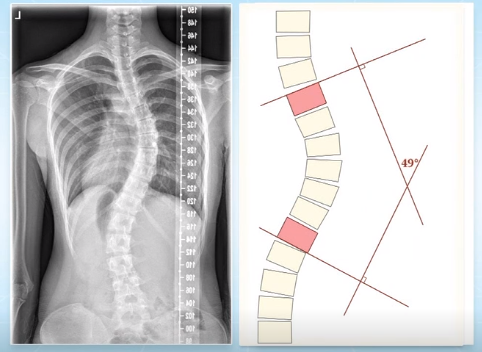

脊柱側(cè)彎的角度測量